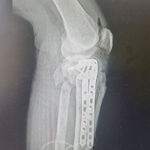

Kończyna górna